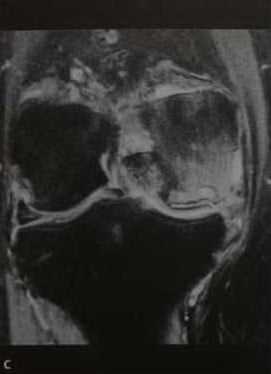

а-d Остеонекроз коленного сустава у женщины 65 лет. Внезапное возникновение болевого синдрома без травмы. Рентгенологическое исследование коленного сустава: (а) в прямой проекции, (b) в боковой проекции. Рентгенопрозрачные участки (стрелка) с окружающим склерозом, дегенеративными изменениями и уплощение суставных поверхностей.

(с), (d) МРТ. Фронтальное протонное плотно-взвешенное изображение с подавлением МР-сигнала от жировой ткани (с) и сагиттальное Т1 -взвешенное (d) изображение. Перифокальный отек и линейные субхондральные участки являются признаками стрессового перелома с дегенеративными изменениями в медиальном мениске.